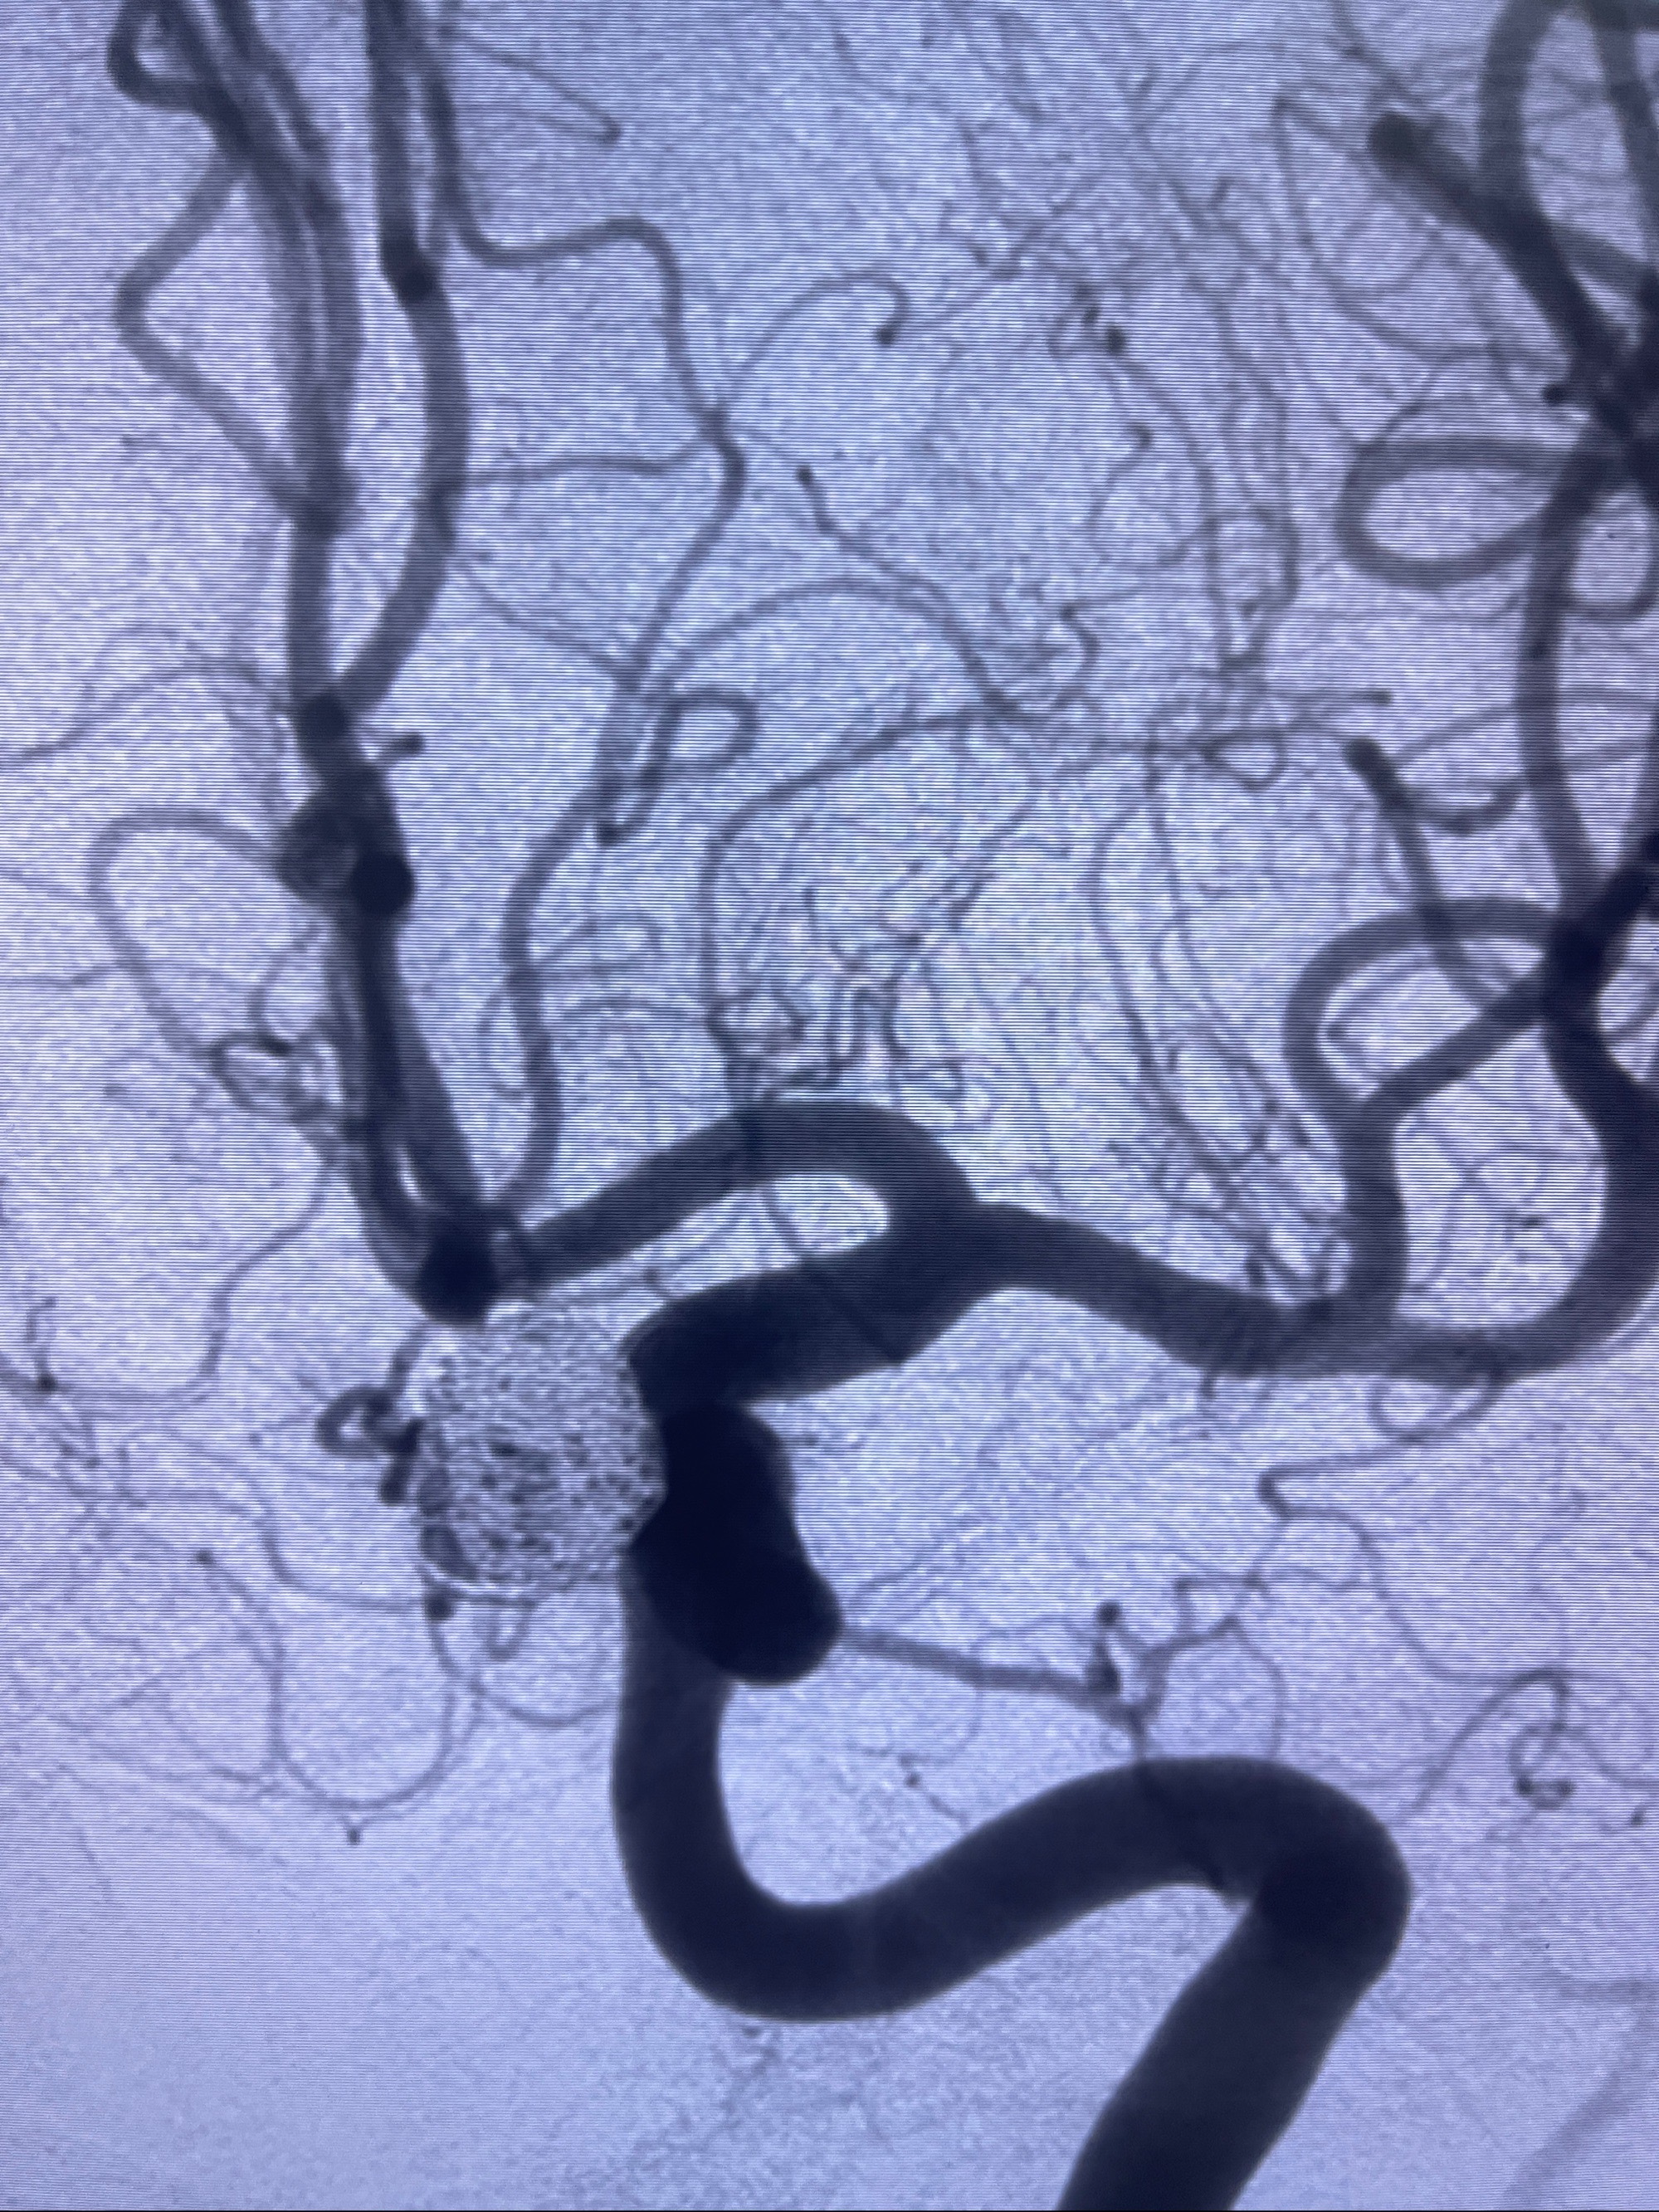

密网支架辅助栓塞

- Tubridge 4.0-20mm密网支架

- 加奇微弹簧圈:7*30/6*20/5*20/2*8

术后3D显示支架贴壁佳